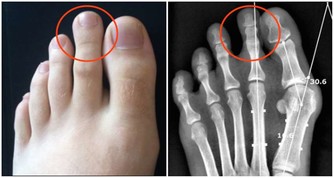

三月初,我的頸椎出了一點問題,整個人的精神狀態都很不好,睡覺不舒服,也不能長期坐在電腦面前。

我在想著,我還這麼年輕,頸椎怎麼就開始出問題了?那以後我怎麼辦?

可是我又非常清楚,長期在電腦面前工作,頸椎出問題也在預料之中。

再想起頸椎不舒服的那段時間裡,我明白這是對我的一種預警,警告著我:如果你再這樣下去,你的頸椎真的會出問題的。

直到現在,我都不會讓自己長時間緊繃在電腦面前了。寫稿斷片的時候,我就站起來活動活動,伸伸懶腰,讓肌肉不那麼緊繃,或者聽會音樂,放鬆一會兒。